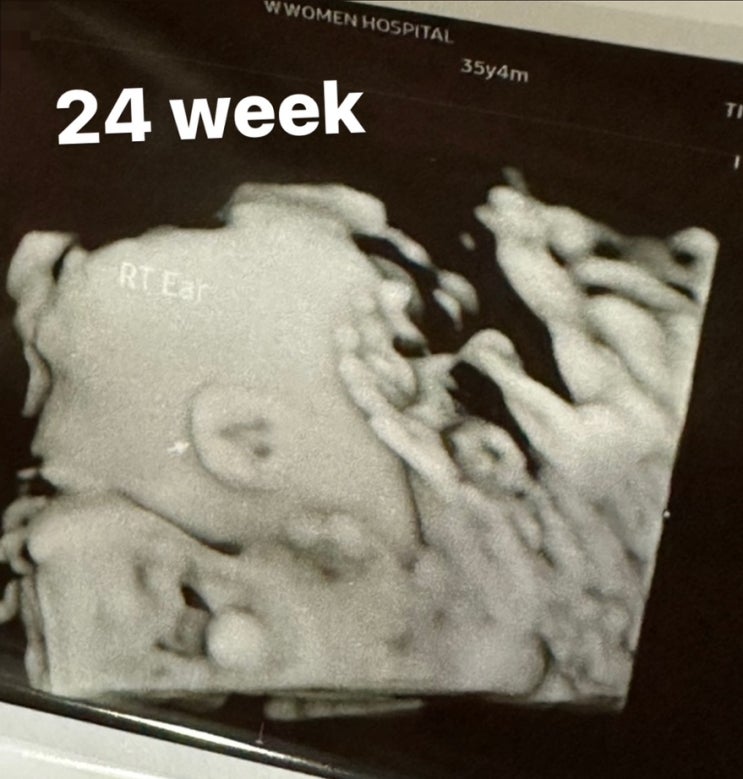

(임신 24주 일상)임신중기 배뭉침, 배통증, 임당검사, 정밀초음파,임산부 영양제

24주 증상 : 태동 잦음, 배뭉침있음 몸이 무거움, 배가 따끔따금 통증이 간혹 있음 24주에는 임당검사와 정...